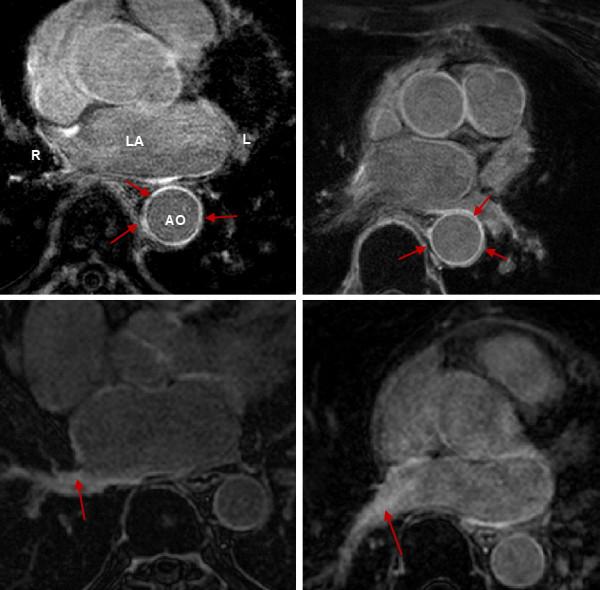

Late Gadolinium enhancement (LGE) cardiovascular magnetic resonance (CMR) imaging can be used to visualise regions of fibrosis and scarring in the left atrium (LA) myocardium. This can be important for treatment stratification of patients with atrial fibrillation (AF) and for assessment of treatment after radio frequency catheter ablation (RFCA). In this paper we present a standardised evaluation benchmarking framework for algorithms segmenting fibrosis and scar from LGE CMR images. The algorithms reported are the response to an open challenge that was put to the medical imaging community through an ISBI (IEEE International Symposium on Biomedical Imaging) workshop.

迟发钆增强(LGE)心血管磁共振(CMR)成像可用于可视化左心房(LA)心肌中的纤维化和瘢痕区域。这对于房颤(AF)患者的治疗分层以及射频导管消融(RFCA)后的治疗评估非常重要。在本文中,我们提出了一个用于从 LGE CMR 图像分割纤维化和瘢痕的算法的标准化评估基准。报告的算法是对通过 ISBI(IEEE 生物医学成像国际研讨会)研讨会向医学成像社区提出的公开挑战的回应。